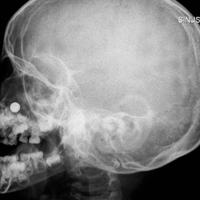

הגולגולת בצילום הדמיה והסוללה התקועה באף

מיד עם הגעתו של דניאל לחדר המיון הוא נבדק ע"י צוות מומחי אף אוזן וגרון ועבר בדיקות הדמיה.

ובדיקת ההדמיה (בתמונה) הראתה בבירור סוללה תקועה בתוך הנחיר הימני בין הטורבינה התחתונה למחיצת האף וגרמה לכוויה כימית בתוך ריריות האף והפרשה של נוזלי הסוללה. "הפעוט הועבר לחדר הניתוח והסוללה הוצאה בהצלחה בסיוע צוות מרדימים בכיר ע"י מלקחיים סטריליים שנועדו לשלוף גופים זרים באופן בטוח ומוגן", הוא מתאר. לאחר שהפעוט התעורר מההרדמה בוצעה שטיפה של האף עם חבישה ואנטיביוטיקה ובהמשך הוא ישוחרר לביתו.